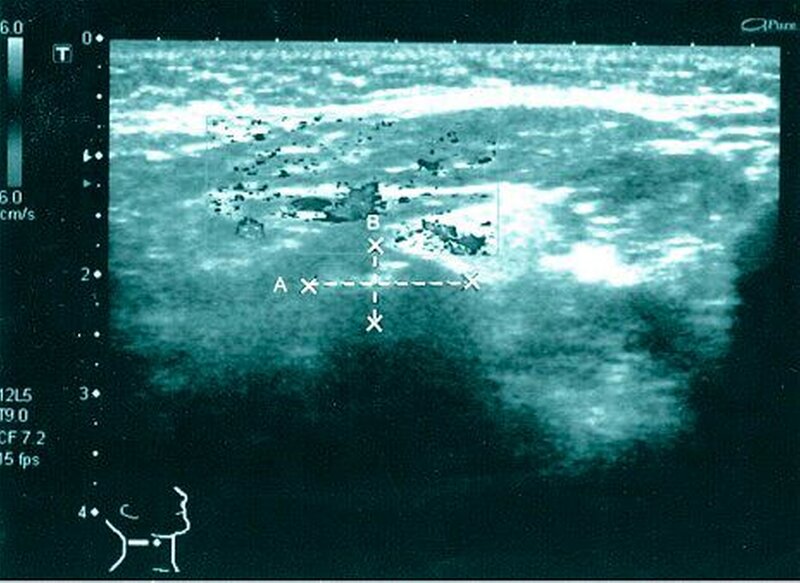

Aufgrund des ausgeprägten Lokalbefunds (Abbildung 2) konnte die Verdachtsdiagnose klinisch durch die bimanuelle Palpation des Mundbodens bestätigt werden. Die Bildgebung mittels Sonografie komplettierte das diagnostische Procedere (Abbildung 3). Nebenbefundlich nahm die Patientin aufgrund von anamnestisch rezidivierenden, tiefen Beinvenenthrombosen Rivaroxaban (Xarelto®, 20 mg, 1–0–0) zur Antikoagulation ein.

Die Antikoagulation wurde unverändert weitergeführt, wobei der Eingriff am Morgen vor der Einnahme der nächsten Tablette stattfand. Nach Schienung des Warthon-Gangs via Kunststoffröhrchen zur Identifikation desselben erfolgten die Eröffnung des Ganges sowie die Darstellung und Bergung des Speichelsteins (Abbildungen 4 und 5) bei einer Größe von 2 cm x 1,3 cm. Das intraoperativ geborgene Konkrement (Abbildung 6) konnte eindeutig als Speichelstein (Sialolith) identifiziert werden. Eine weiterführende histopathologische Dignitätsklärung war nicht erforderlich. Der eröffnete Ausführungsgang wurde über nicht resorbierbare Nähte im Sinne einer Marsupialisation an den Mundboden angesteppt und so die neue Mündung nach proximal verlegt.

Neben der klinischen bimanuellen Tastuntersuchung des Mundbodens beinhaltet die traditionelle diagnostische Vorgehensweise die Sonografie als Goldstandard [Yoshimura et al., 1989] sowie die Röntgenbildgebung zur genauen Lokalisationsbestimmung bei unklaren Befunden [Yoshimura et al., 1989; Yuasa et al., 1997; Iro und Zenk, 2003; Capaccio et al., 2007]. Die früher regelmäßig durchgeführte Sialografie ist im Zeitalter der hochauflösenden Sonografie in den Hintergrund geraten und wird nur noch in Ausnahmefällen durchgeführt.

Goldstandard der Bildgebung bei Sialolithiasis der Gl. submandibularis ist die Sonografie. Bei unklarem Befund sollte eine röntgenologische Bildgebung erfolgen.